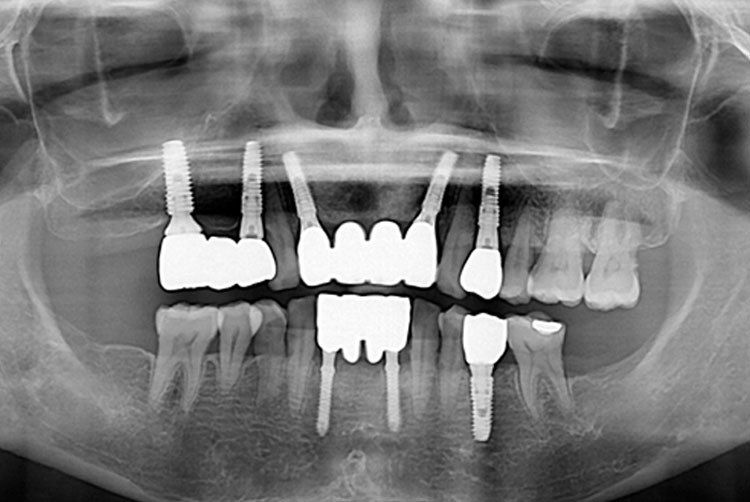

김소완_후.jpg

치료후 : 2018-09-27

세종치과는 많은 환자와 다양한 케이스를 바탕으로 항상 편안한 임플란트 수술을 제공하고자 노력하고,

오래동안 튼튼히 쓸 수 있는 임플란트 수술을 가장 큰 목표로 삼고 있습니다.